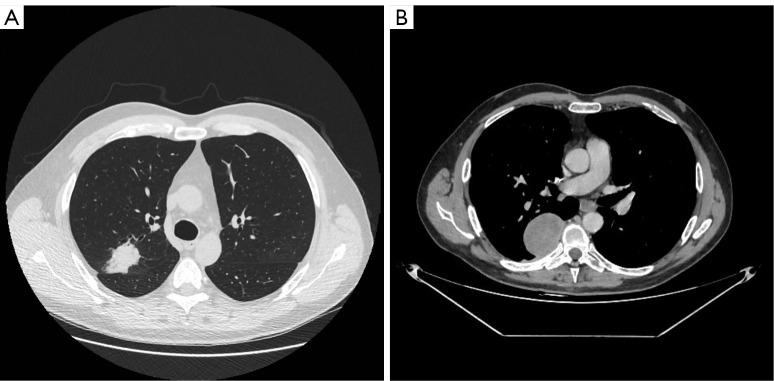

A 54-year-old man, never-smoker and with no previous medical history, underwent right superior lobectomy with lymph node resection for a pT3N1M0 [stage IIIA, tumor-node-metastasis (TNM) 8 edition] adenocarcinoma. Programmed death-ligand 1 (PD-L1) negative with an EGFR exon 19 deletion. The patient received 4 cycles of adjuvant chemotherapy before starting adjuvant osimertinib 80 mg. After 35 months of adjuvant osimertinib the patient had a local recurrence and the re biopsy showed an SCLC transformation, underlining the importance of careful surveillance and biopsy at the time of recurrence in EGFR-mutated NSCLC.

this case report provides evidence of SCLC transformation while on adjuvant osimertinib, in a pT3N1 EGFR, RB1 and TP53-mutated pulmonary adenocarcinoma. This highlights the importance of biopsy on recurrence and the transformation potential of the EGFR, RB1 and TP53-mutated adenocarcinomas.